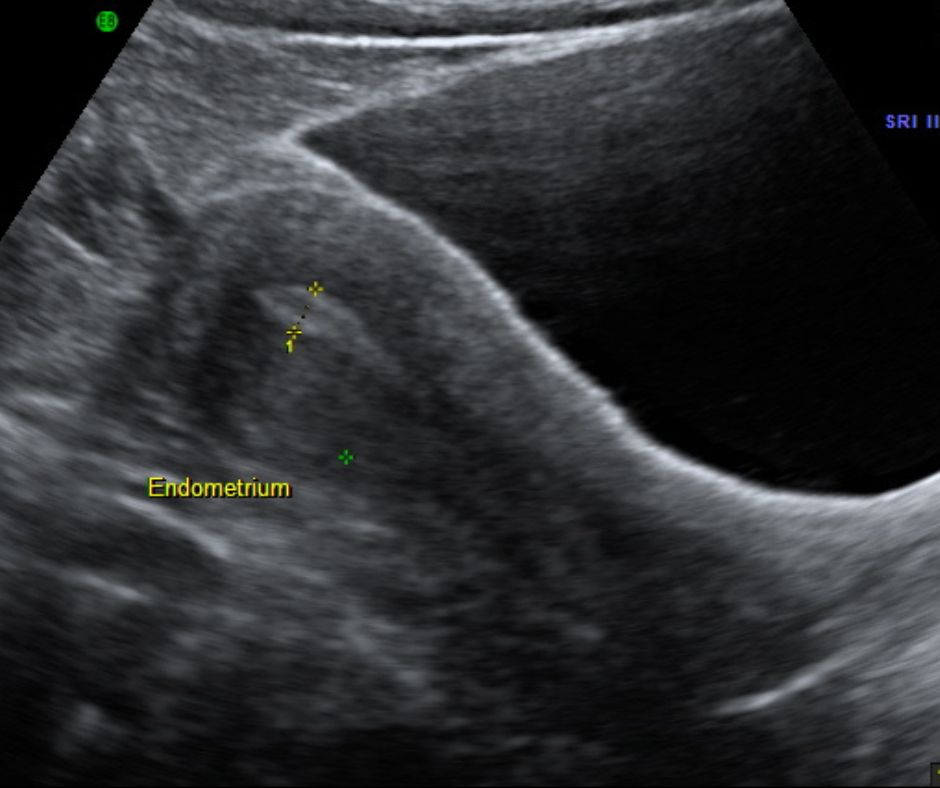

Endometrial Thickness Scan

As the name suggests, this scan measures the width of the lining of the uterus (the endometrium) and its condition. An examination of this kind can detect changes that happen during the monthly cycle and estimate ovulation; it can also monitor responses in the womb to fertility drugs. The purpose is to predict when ovulation will peak hence to suggest a timing to increase the patient’s probability of conceiving, whether naturally or through fertility treatment.